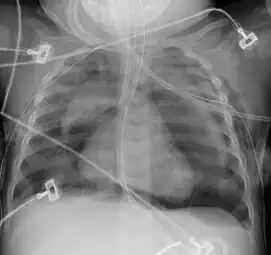

Pneumomediastinum is uncommon and occurs when air leaks into the mediastinum. The diagnosis can be confirmed via chest X-ray showing a radiolucent outline around the heart and mediastinum or via CT scanning of the thorax.